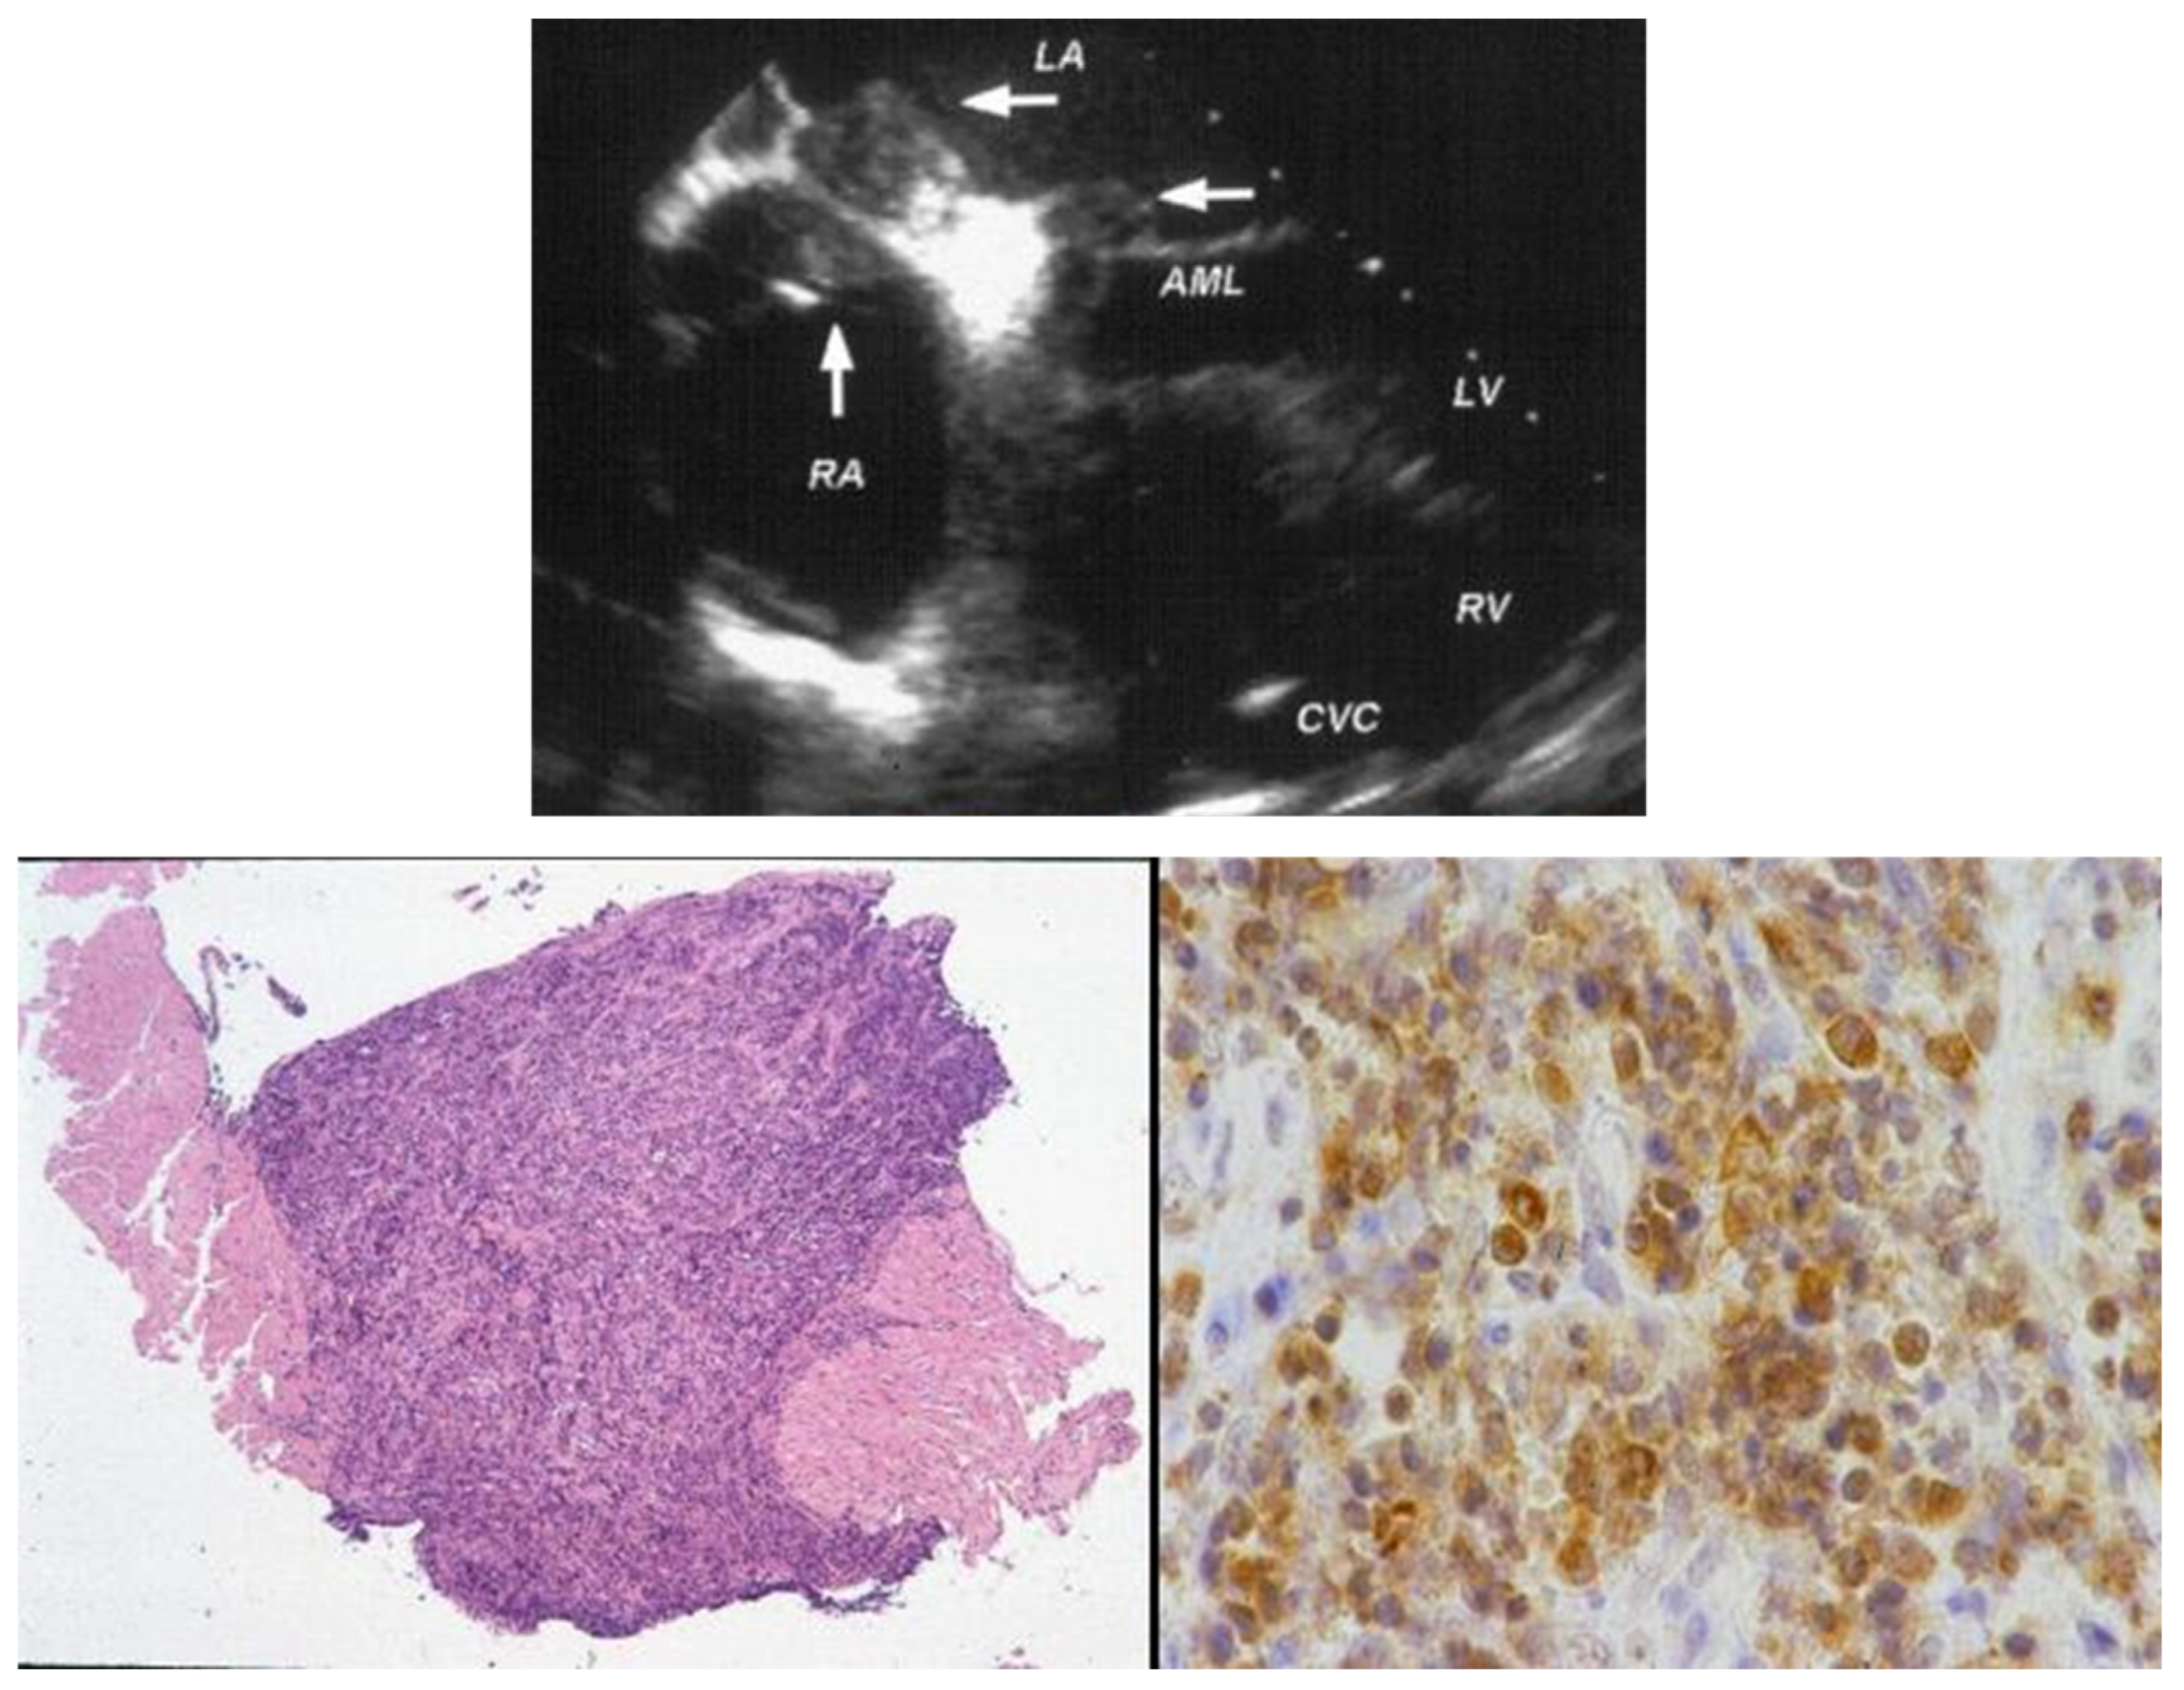

7. Clinical Indications of Endomyocardial Biopsy

9. Diagnosis of ACM Through Endomyocardial Biopsy and Infiltrative Disease as Amyloidosis